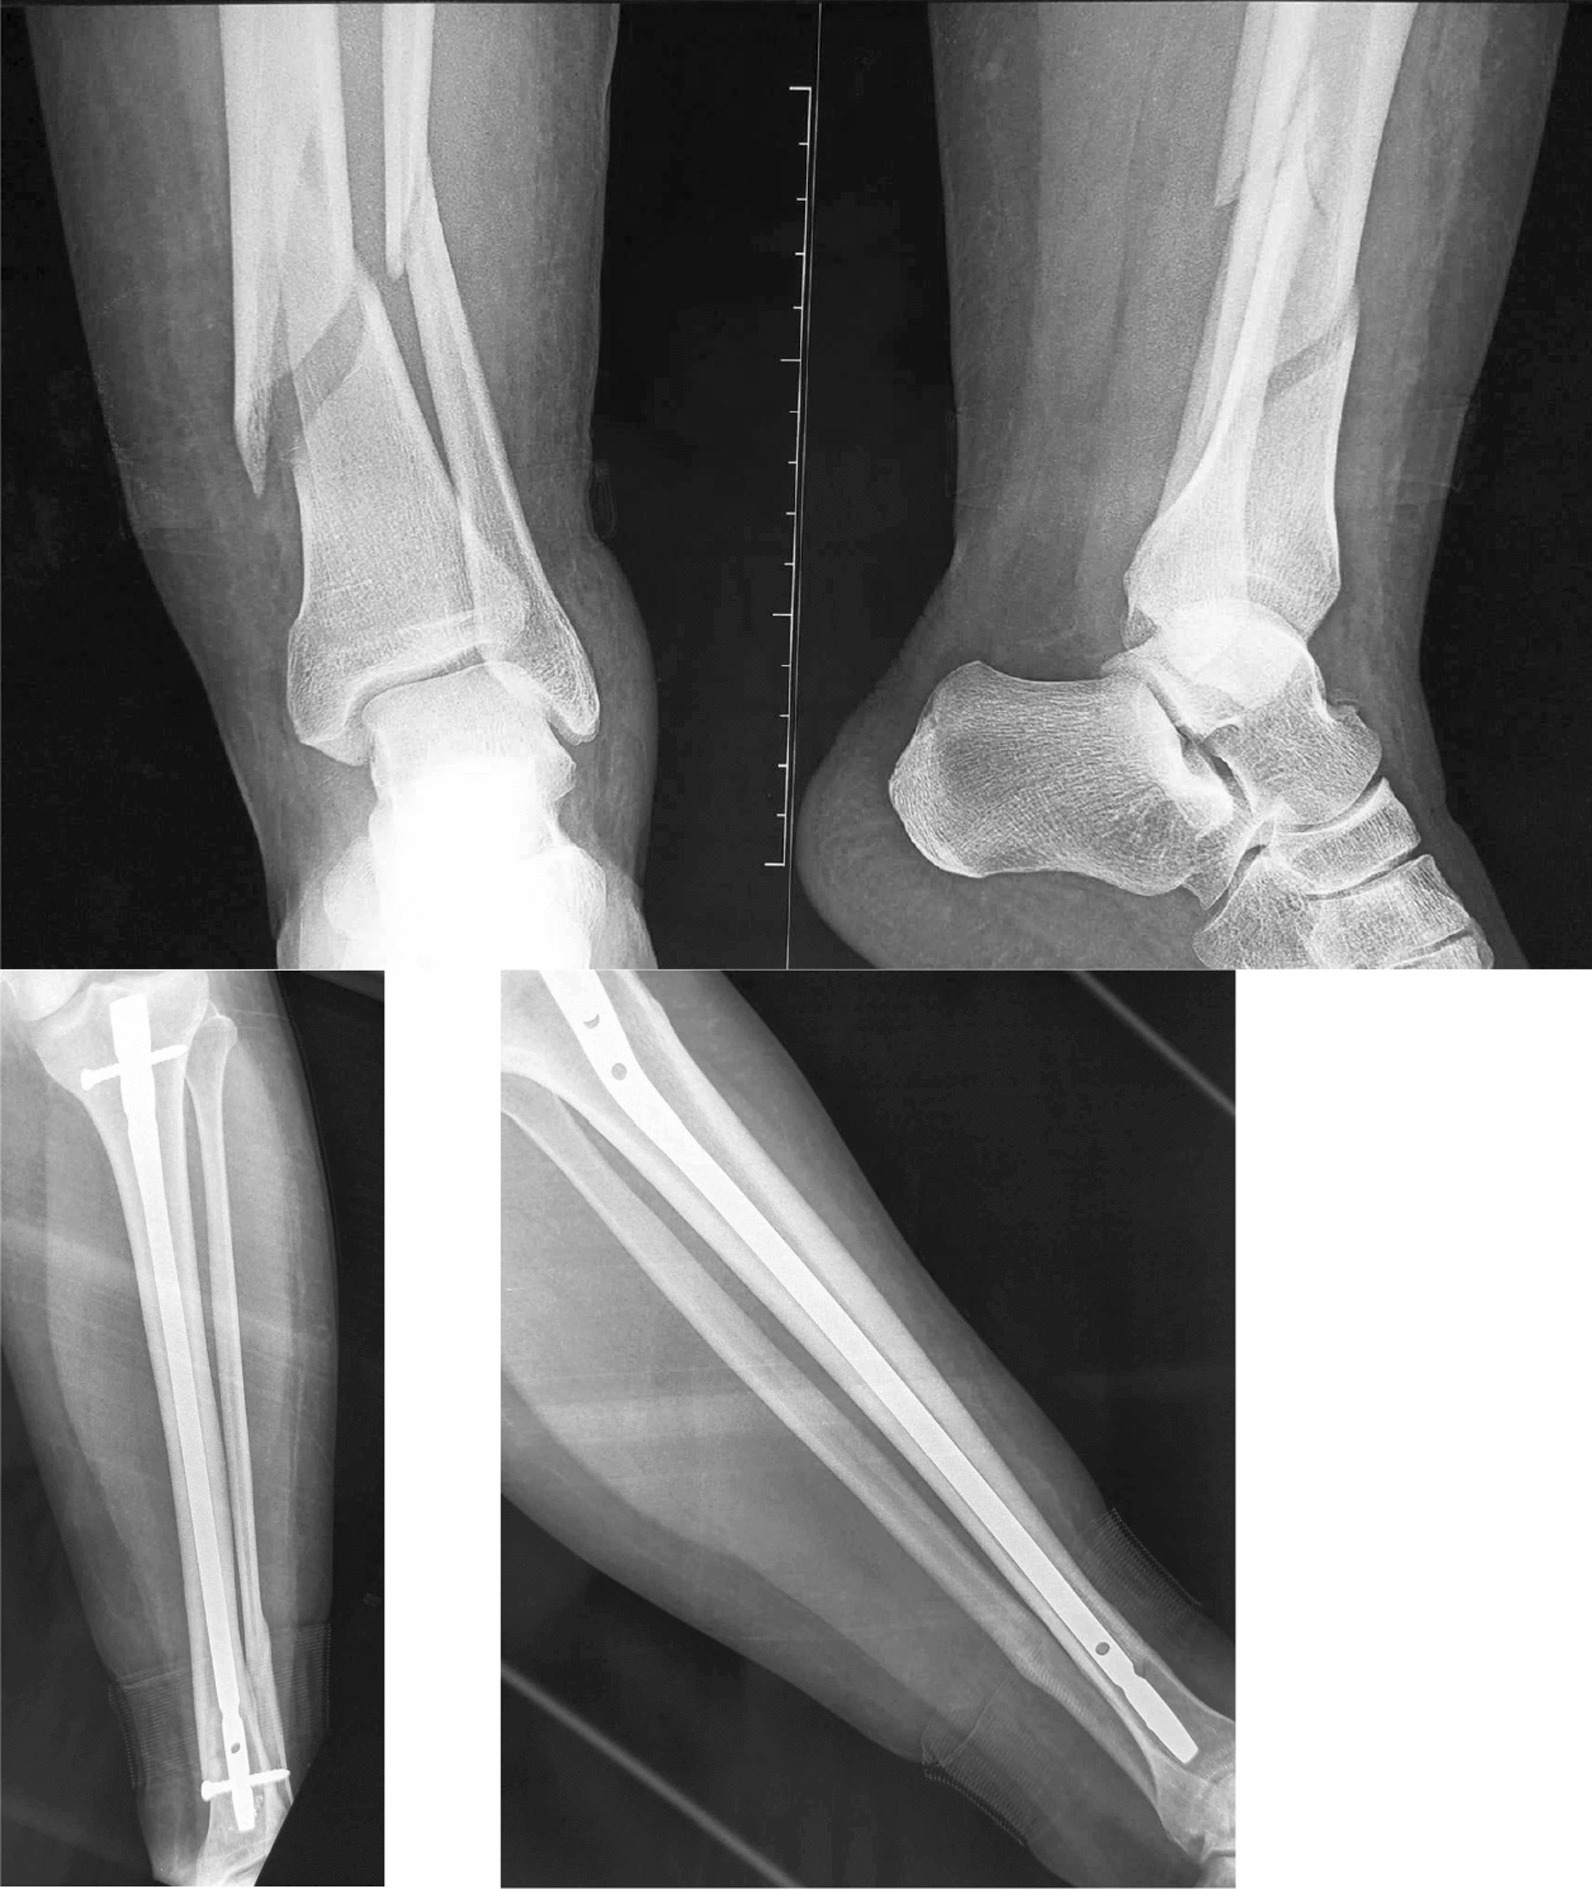

The mean follow-up was 48 months (range from 18 months to 8 years). All fractures in our study ultimately healed, with an average healing time of 4.3 months (range from 45 days to 12 months) (Fig. 3). Delayed union was observed in 11.1% of the patients.

Fig. 3.

Distal tibia fracture, treated by intramedullary nailing, healed with good alignment

At the last follow-up, malunion occurred in 13 cases (14.4%). Among these cases, there were seven cases of varus misalignment, one case of associated limb shortening, one case of valgus misalignment and four cases of apex anterior angulation including one associated external rotation (Fig. 4).

Fig. 4.

Distal tibia fracture associated a fibula fracture (a and b) treated by intramedullary nailing with a double block screws with an evolution toward malunion